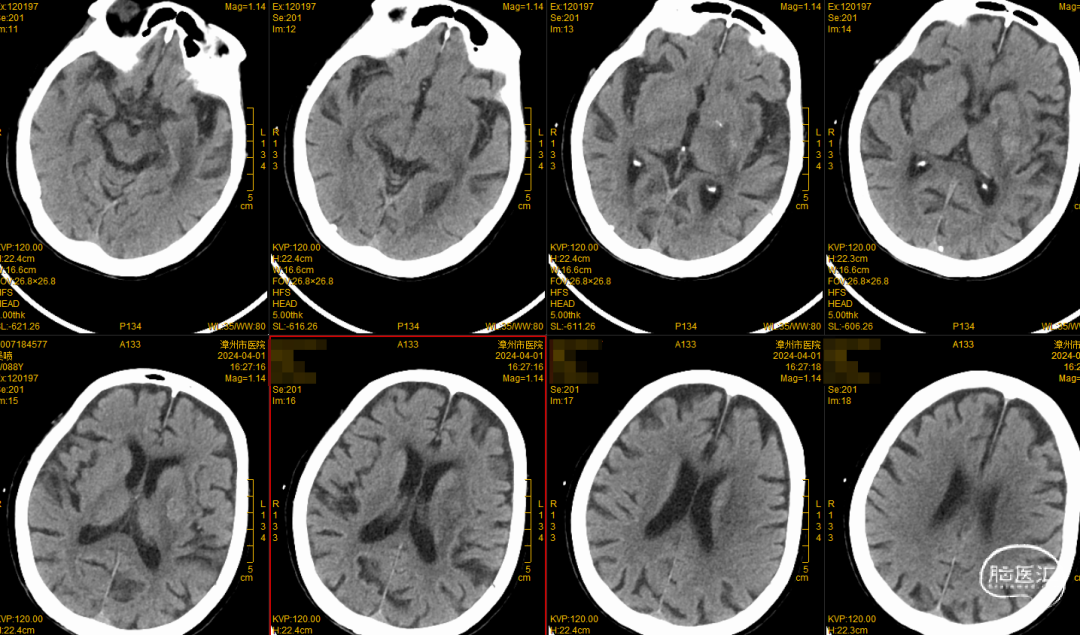

颅脑CT平扫

复查颅脑CT提示渗血吸收,予5mg利伐沙班抗凝。